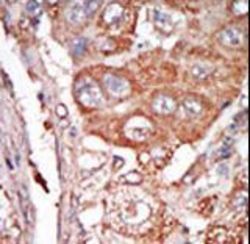

- Formalin-fixed and paraffin-embedded human cancer tissue reacted with the primary antibody, which was peroxidase-conjugated to the secondary antibody, followed by DAB staining. This data demonstrates the use of this antibody for immunohistochemistry; clinical relevance has not been evaluated. BC = breast carcinoma; HC = hepatocarcinoma.

- Formalin-fixed and paraffin-embedded human cancer tissue reacted with the primary antibody, which was peroxidase-conjugated to the secondary antibody, followed by DAB staining. This data demonstrates the use of this antibody for immunohistochemistry; clinical relevance has not been evaluated. BC = breast carcinoma; HC = hepatocarcinoma.

- Formalin-fixed and paraffin-embedded human cancer tissue reacted with the primary antibody, which was peroxidase-conjugated to the secondary antibody, followed by DAB staining. This data demonstrates the use of this antibody for immunohistochemistry; clinical relevance has not been evaluated. BC = breast carcinoma; HC = hepatocarcinoma.